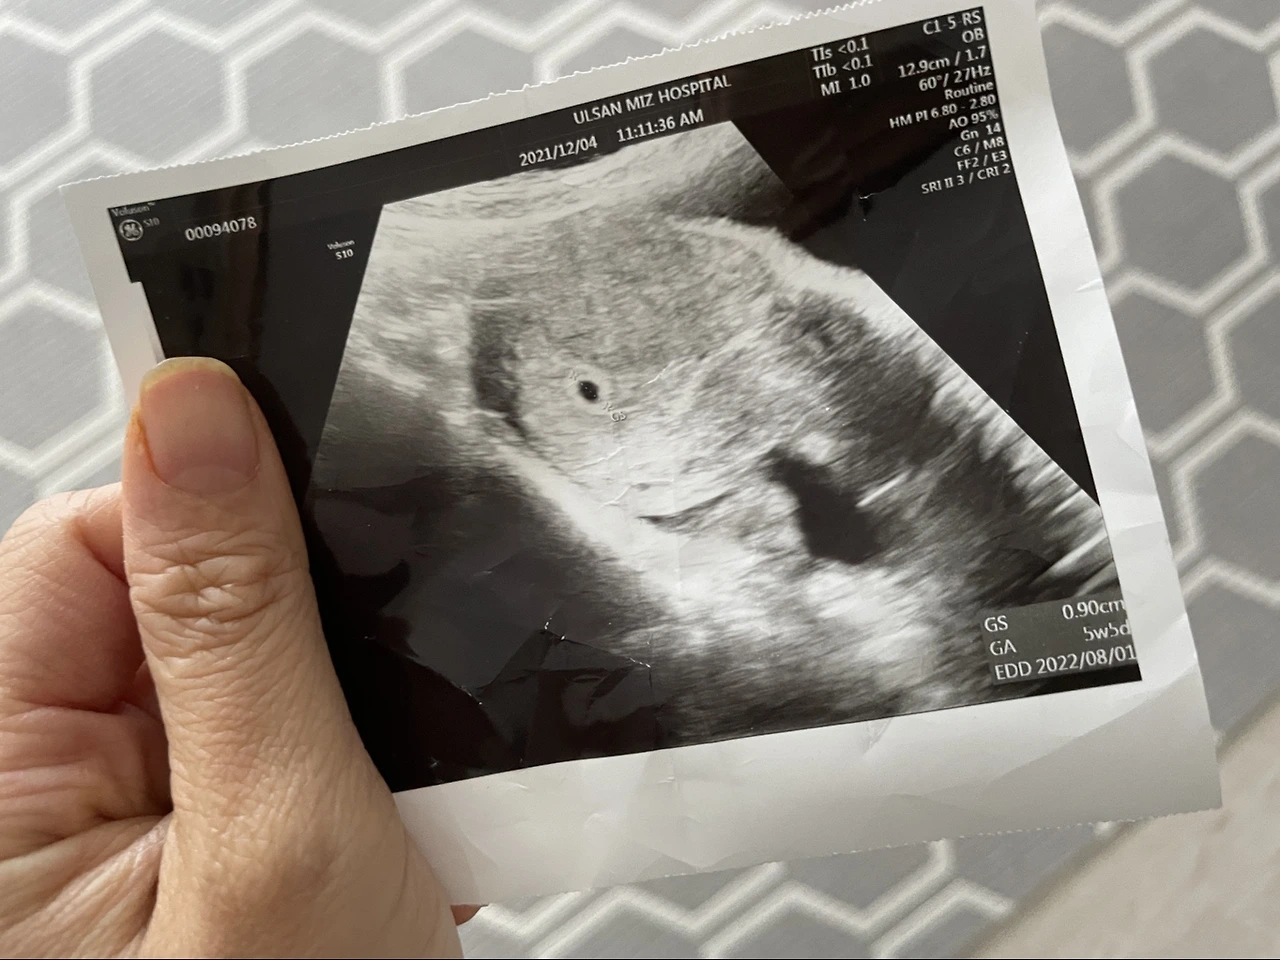

임신 처음 알고 병원에 갔을 때

아기집에 아무것도 안보여 걱정했지만 다음주 아기와 심장소리까지!